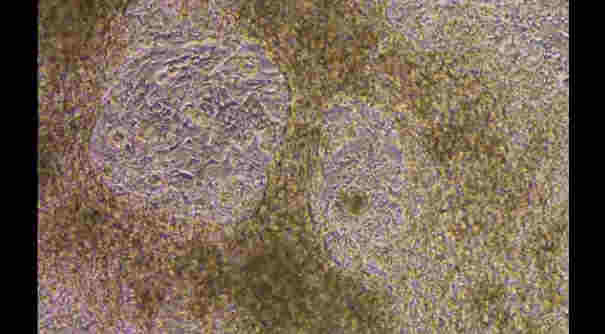

關于電子煙的研究正在穩步增長,但對于這種習慣,包括其潛在的長期后果,仍有許多未知。南佛羅里達大學的一項新研究探討了吸入這些液體中使用的汽化香精的潛在影響。香精分子進入血液并進入心臟,在那里發現它們對HL-1細胞具有毒性,至少在小鼠中是如此。

利用從人類干細胞中提取的心臟細胞,該研究還發現證據表明,這些口味電子煙煙油可能具有比單獨尼古丁更強的心臟毒性作用。年輕的小鼠每周暴露在電子煙中5天,持續10周,結果發現正常的心率變異性受到干擾。